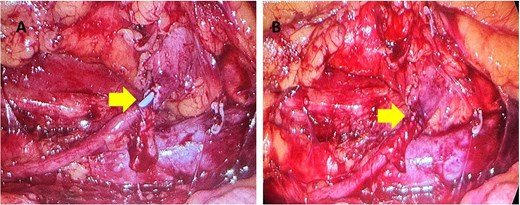

One month later a laparoscopic repair of the RU was completed. Under general anaesthetic the patient was placed right side up. A pneumoperitoneum was created with the Kii Fios first entry system and a 5 mm camera, two additional ports were used (5 mm and 12 mm). The ascending colon was mobilized medially and the IVC identified. Careful dissection allowed identification of the RU (Fig. 4). The ureter was fully mobilized behind the IVC, then divided and spatulated. Two 4.0 vicryl stay sutures were used to anastomose the apex of the spatulated ureter to proximal ureter. The posterior uretero-ureteral anastomosis was performed with interrupted 4.0 vicryl sutures. A 6 French (Fr), 24 cm JJ stent was placed into the ureter and the anterior anastomosis was performed again with interrupted 4.0 vicryl sutures (Fig. 5A and B). A 16Fr non-suction drain and a 16Fr urinary catheter were placed.

Mobilization of the ascending colon medially has exposed the IVC (red arrow) and the ureter (yellow arrows). Note how the ureter passes behind the IVC. The gonadal vein needed to be removed. Note the hem-O-Lok clip on the vein coming off the IVC.